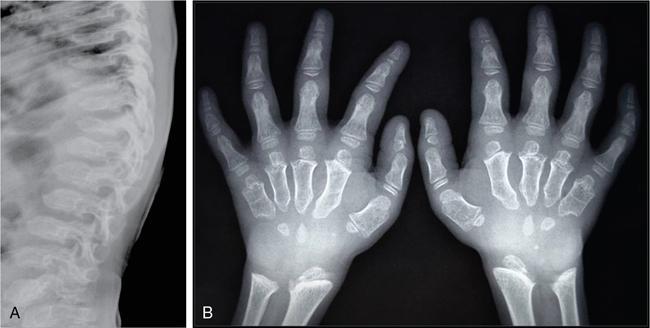

MISCELLANEOUS PAEDIATRIC RADIOGRAPHY – TECHNIQUES AND INTERPRETATION: SKELETAL SURVEY Padma V. Badhe The skeletal survey, generally performed in children, is a set of radiographs done in order to evaluate the entire skeleton. A skeletal survey, commonly used to evaluate skeletal dysplasias, acquired metabolic disorders and suspected child abuse, is still the key radiological investigation for the same. Hence, an explicit understanding of the technique along with the common disorders forms the basis of making a diagnosis in these paediatric pathologies. A skeletal survey is done for various skeletal dysplasias, non-accidental injury (battered baby syndrome) and suspected child abuse. It can also be done in cases of metabolic bone diseases, disseminated infections, multiple myeloma, eosinophilic granuloma. It is also used in evaluation of metastatic bone diseases and polyarticular arthropathy. Orthogonal views of the skull, spine, pelvis and one extremity are taken, preferable in standing position. For preterm babies/newborns, AP and lateral views of babygram may be taken. Projections: For skeletal dysplasias: Additional views: Both extremities may be taken if epiphyseal abnormalities and limb asymmetry is present. Focused views for specific pathologies may be taken. When a diagnosis remains uncertain, 1 year follow up is usually recommended. For preterm babies/newborns: AP and lateral views of babygram may be taken with additional specific views for extremities. For suspected non-accidental injury (NAI): AP and oblique view of chest is taken for better evaluation of the ribs. AP view of abdomen with pelvis. Both upper and lower limbs are evaluated. In lower limbs, two projections in AP and lateral (one with both femur including hip and knee joints; and another for foot and ankle) is taken. AP and lateral views of whole spine, skull. Oblique view of hands. A babygram should be avoided in cases of NAI, as subtle fractures are easily missed. Proper legal documentation while taking the views is very important and ideally two health care professionals must be present. For metabolic disorders: entire skeletal survey is usually not required. Specific views of hands, knees and spine may be taken with additional views depending on the suspected pathology. Centring point: Varies according to the part being examined. Angulation, collimation and orientation: Varies according to the part being examined. Images must be well collimated to obtain lower radiation dose. Detector size: Varies according to the part being examined: 8″ × 10″, 10″ × 12″, 11″ × 14″. Exposure: Ideally high kVp images are taken to reduce radiation dose. But in suspected NAI, low kVp/high mA images are recommended to better demonstrate findings. SID (Source Image Distance):100 cm Grid: Grids are not routinely used to image spine, pelvis, skull and abdomen in children. Radiation dosage: 0.3–3 mSv Essential image characteristics: Adequate spatial resolution, high signal to noise ratio, low kVp (50–70) for high contrast should be done. Excellent bone and soft tissue details are required. The presentation of skeletal dysplasia can range anywhere from minimal stunting of growth and bowing of limbs to severe dwarfism and multiple fractures. Knowledge of the commonly encountered dysplasias with an approach to arrive at a diagnosis is vital in any Radiologist’s practice The following flow chart summarizes the classification of important skeletal dysplasia: The following table summarizes the various dysplasias affecting the axial skeleton: TABLE 7.5.1.1 The following flow chart summarizes the working approach to skeletal dysplasias: Osteopetrosis (Albers-Schonberg disease/Marble bone disease) (Fig 7.5.1.1): Osteopetrosis clinically presents with anaemia/thrombocytopenia or cranial nerve compression. Radiological features include generalized increase in bone density with loss of medullary space. However, cortico-medullary appreciation with cortical thinning is also rarely seen. Bone within bone appearance with Erlenmeyer flask deformity is also noted. Pyknodysostosis (Figs. 7.5.1.2 and 7.5.1.3): patient presents with short stature. Unlike osteopetrosis, there is no anaemia. Radiographs show generalized increase in bone density with preserved medullary canal. There is mandibular hypoplasia with obtuse angle. Acro-osteolysis is also a feature. Dental caries with osteomyelitis of the jaw may be seen. Sclerosing dysplasia presenting as wavy undulating new bone formation. Usually monomelic, lower limb and along one side. The classic appearance is described as Dripping candle Wax sign. It is a Sclerosing dysplasia with radiological features of symmetric juxta-articular involvement in epimetaphyseal region. They are 1–10 mm in diameter and uniform in size. No metabolic activity is seen on bone scans. This skeletal dysplasia shows diffuse decrease in bone density with paper-thin cortex. Fractures heal in normal time but shows callus with poorly cellular matrix. Wormian bones and enlarged sinuses may be seen. Codfish vertebra (Biconcave vertebra) may be seen. Metaphyseal corner fractures are not seen in osteogenesis imperfecta that helps to differentiate it from battered baby syndrome. There are four types of OI out of which type one is most common (Figs. 7.5.1.6 and 7.5.1.7). The radiological features of MPS include Osteopenia and Universal platyspondyly. The intervertebral disc spaces are maintained. Proximal pointed metacarpals is an important radiological finding. Hurler’s syndrome show anteroinferior beaking with short and wide metacarpals. Varus deformity of humerus is characteristically seen in Hurler’s syndrome (Fig. 7.5.1.8). Mental retardation & corneal clouding is seen in Hurler’s syndrome whereas these Hunter’s disease has normal intelligence with no corneal clouding. Morquio’s syndrome shows central beaking (Fig 7.5.1.9). This skeletal dysplasia shows normal bone density with rhizomelic limb shortening and normal trunk. Narrowing of spinal canal is classically seen with decrease in the Interpedicular distance caudally. Other radiological features include trident hand (separation of middle & third fingers), Champagne glass pelvis (short, flat ilia and small sciatic notch), bullet nose vertebra and overexpansion of skull with narrow foramen magnum (Fig. 7.5.1.10). This skeletal dysplasia is characterized by normal bone density with dwarfism and normal craniofacial skeleton. The interpedicular distance is normal. There is severe platyspondyly with anterior tonguing (disappears at older age). Other radiological features include increased disc space, short stubby metacarpals, small irregular epiphysis and widened metaphysis. Anterior tonguing is a feature of Pseudoachondroplasia. This form of skeletal dysplasia involves the spine and epiphyses (Fig. 7.5.1.11). There is normal bone density with rhizomelia. Spine and Pelvis can be involved. Premature osteoarthritis can be seen. The other characteristic features include Platyspondyly and small irregular epiphysis. There are two forms Spondyloepiphyseal dysplasia Congenital and Spondyloepiphyseal dysplasia Tarda. Spondyloepiphyseal dysplasia Congenita is Autosomal dominant and shows pear-shaped vertebrae. Spondyloepiphyseal dysplasia Tarda is X Linked recessive with heaped up vertebrae. It has two forms. The first form is Conradi Hunermann syndrome which is autosomal dominant characterized by asymmetric limb shortening with metaphyseal flaring (Fig. 7.5.1.12). The Autosomal recessive form is Fatal in first few years. Rickets: Rickets refers to deficient mineralization of the growth plate in the paediatric population due to deficiency of vitamin D. In an immature skeleton, there is abnormal mineralization at the zone of provisional calcification in the metaphysis due to osteoid deposition resulting in widening of the growth plate. The features of rickets include fraying, splaying and cupping (Fig. 7.5.1.13). Fraying denotes indistinct margins of the metaphysis whereas splaying denotes widening of metaphyseal ends. Term ‘Cupping’ is used for increased concavity of the metaphysis. These findings are typically seen involving areas of active growth (e.g. distal femur and proximal tibia in the knee) Bowing is a result of associated osteomalacia leading to weakening of weight-bearing lower limb bones. Other bone deformities such as genu valga, genu varum, protrusio acetabuli can also be seen. The lower ribs may also be drawn inwards inferiorly by the attachment of the diaphragm this is called Harrison’s sulcus. Scurvy: Scurvy is a result of dietary deficiency of Vitamin C (ascorbic acid). The classic presentation is that of a patient with an increased bleeding tendency and osteopenia with poor wound healing. Features of scurvy include generalized osteopenia with cortical thinning termed as ‘pencil-point’ cortex. Other radiological findings include the periosteal reaction due to subperiosteal haemorrhage. Expansion of the costochondral junctions occurs forming scorbutic rosary. Bleeding into the joint spaces may result in hemarthrosis. Circular, opaque radiologic shadow surrounding epiphyseal centres of ossification may result from bleeding (Wimberger ring sign) (Fig. 7.5.1.14). Frankel line may be seen. It represents dense zone of provisional calcification. Lucent metaphyseal band is seen underlying Frankel line called as Trümmerfeld zone. Metaphyseal spurs may be seen that result in cupping of the metaphysis (Pelkin spur). Pelkin fracture (metaphyseal corner fracture) can also be seen. Images obtained must be of good resolution with adequate bone and soft tissue details. Additional views: They have already been described in positioning. CT Brain in can be done in cases of NAI to look for subdural hematomas. A skeletal survey is the first-line imaging modality for evaluation of skeletal dysplasia, nonaccidental injury and metabolic bone diseases. The skeletal survey must be tailored according to the respective indication. It helps to characterize syndromic patterns in skeletal dysplasias, with evaluation of complications. In cases of diagnostic dilemmas, additional focused view and occasionally yearly follow-up is recommended. A high index of suspicion is needed in utilizing skeletal survey as a diagnostic modality in NAI. At the same time, one must also remember the legal and social implications of making this diagnosis. BABYGRAM Babygram is a colloquial term used for a radiograph of the whole body of a newborn or just the chest and abdomen (thoracoabdominal babygram) on a single image. As the name suggests it is a rather non-targeted study. It is most commonly requested after line placement. Evaluation of skeletal abnormalities in a deceased foetus is typically performed using anteroposterior and lateral views of a babygram. It helps in pointing out skeletal causes of death in stillborn or dead foetuses. This will help the treating physician and parents understand the reason for baby’s death. This will also help in future genetic counselling of the couple. Sometimes chest or abdominal radiographs of the baby are requested but due to radiographers error or inexperience with small babies, there is inclusion of the region not to be assessed leading to a false babygram. Babygram is most frequently done after line placement in neonates, to view the position of the umbilical vein or artery catheter and to confirm appropriate placement. It is a useful modality in skeletal dysplasias (Fig. 7.5.1.15) like osteogenesis imperfecta, thanatophoric dysplasia and chondrodysplasia punctata. It can also be used for skeletal deformations probably caused by foetus akinesia and in cases of Caudal regression syndrome. In stillborn foetuses, it is used for evaluation of skeletal dysplasias prior to an autopsy (Fig. 7.5.1.16). It is also used in screening for surfactant deficiency and in cases of Necrotizing Enterocolitis in preterm babies where it can help to see the bowel dilatation, intramural and portal venous gas. It can be done in aneuploidies like trisomy 18 and in cases of sudden infantile death syndrome. All the essential equipment and room need to be prepared including the exposure factor. This should be done prior to placing the baby on the table to prevent any neonatal heat loss. Ensure that the baby is correctly identified. Give brief explanation to the patient’s parents regarding the procedure, its risks and benefits. Ensure that the accompanying relative is not pregnant (if female). Parents/guardians/nurses should be instructed to hold the baby with arms above the head and legs straight down. Sandbags/tapes can be used to immobilize the baby. Avoid taking the radiograph when baby is crying. Normal appearance: The endotracheal tube should lie in the lower third of trachea, distance can vary with position of baby’s head. Umbilical artery catheter has an inferior dip along the internal iliac artery, which then turns superiorly along the aorta. The tip should lie in the mid-thoracic aorta (T6–T10) or lower (L3–L4) away from aortic branches to prevent any thrombosis. Umbilical venous catheter does not have the inferior curvature, but rather a posterolateral angulation to the right near the liver through the ductus venosus. The tip should lie in the superior IVC or right atrium at T8/T9 vertebral level (Fig. 7.5.1.17). Portal venous gas may be seen initially after insertion. In a stillborn foetus, the approximate gestation age of the foetus and corresponding ossification centres must be known. In early gestation, the lack of appearance of an ossification centre may be mistaken for skeletal dysplasia. Both chest and abdomen should be included. In a rotated patient, the distance between the spinous process to medial end of clavicles will be asymmetric. The medial end of clavicle should overlap the lung apex, if above, suggests lordotic image. Motion artefacts to be reduced as much as possible. A crying neonate may result in an expiratory film, and hence must be evaluated accordingly. In evaluation of skeletal dysplasias in the newborn, additional views of skull and hand have to be obtained. Baby gram is a useful diagnostic investigation for position of the paediatric umbilical catheters. It helps in general survey in skeletal dysplasia (Fig. 7.5.1.18). It is a simple, effective study in deceased foetus for diagnosis and further counselling, sometimes obviating the need for an autopsy. As baby gram is a non-targeted study, it increases the dose of radiation for the baby. As the exposure settings remain same for the entire body of the baby, the quality of the image decreases. This increases the chances of missing subtle findings. The babygram in a neonate is currently used to localize umbilical catheters. In stillborn fetuses, it is still an important study for documenting and confirming skeletal dysplasias. Understanding the normal appearance as per gestation age and patterns of various common skeletal dysplasias is essential for evaluation. Being a non-targeted study, it should not be used as an alternative study to evaluate the chest or abdomen considering radiation exposure and poorer image quality. INVERTOGRAM Invertogram was first described by Wangensteen and Rice in 1930. It was used as a first investigation to be ordered in evaluation of infants with clinically diagnosed or suspected Anorectal Malformation (ARM). ARM is a serious but surgically treatable congenital malformation with approximate incidence of 1 in 5000 live births. Though the diagnosis of this condition is based on clinical history and physical examination, imaging plays an important role in deciding the type of ARM, and associated complications to aid in management. International classification of anorectal malformations is as follows. Syndromic association is seen as a part of VACTERL defects, trisomy 21 13 and 18, Klippel Feil syndrome, cat eye syndrome etc. The main indication of Invertogram is to evaluate anorectal malformation in a neonate. A radio-opaque marker is placed over the external anal opening. Infant is held inverted by holding both thighs, maintaining this posture for at least 5 minutes before taking an X-ray in true lateral position (Fig. 7.5.1.19). Exposure is made during inspiration. The Invertogram should ideally be done 24 hours after birth as, the rectal gas may not reach the terminal segment if study is done too early. Pubo-coccygeal line (PCL) is drawn from upper border of pubic symphysis (which corresponds to centre of pubic bone on lateral X-ray) to sacrococcygeal junction. I point is the inferior most point of ischial ossification centre. A line which is drawn parallel to PC line passing through the I point is called I line. ‘A’ point is represented by marker placed at anal pit. The position of rectal pouch gas shadow is observed with respect to these lines and appropriate diagnosis is made (Fig. 7.5.1.21). A diagnosis of high ARM is made when gas shadow of rectal pouch is cranial to PCL. If rectal pouch gas shadow is in between PCL and I line, it is called as intermediate ARM and if it is caudal to I line, it is diagnosed as low ARM. Gas in urinary bladder or vagina or beaking of gas shadow of rectal pouch indicates fistula into one of these sites. Associated congenital abnormalities like spinal defects are also looked for in the invertogram (Fig. 7.5.1.22). Invertogram done too early (less than 24 hours) may not demonstrate rectal gas. Meconium plugging the terminal segment gives false position of the rectal gas. Positioning can cause discomfort to child and an irritated crying child actively contracts the sphincter muscles, pushing the gas shadow higher. Rectum may be pulled cephalad due to gravity in inverted position. The rectal gas may escape through an associated fistula. Erroneous interpretation can also occur due to sacral anomalies and when gas in vaginal cavity is misinterpreted as distal rectal gas. Both ischial bones should superimpose and terminal blind loop should be well distended. It is an easily available modality and can be done quickly, does not require additional equipment. It has lesser radiation dose as compared to CT invertogram. It provides a rough guide as to the type of ARM and decides management. Higher localization of obstruction due to various causes like meconium plugging, imaging done too early etc. as described above in pitfalls. It is more uncomfortable to the baby as compared to the prone cross-table lateral view, and a crying baby contracts the puborectalis leading to erroneous results. K. L. Narasimharao et al. modified the technique and proposed cross-table lateral view for evaluation of infants with ARM’s which has shown equal or better information and has now replaced invertogram (Fig. 7.5.1.23). Prone cross-table lateral view is considered equivalent or even better in determining the level of anomaly. Positioning is in this view is prone in genupectoral position (at least for 3 minutes). It is taken in true lateral and during inspiration. The lines used to delineate types of ARM is essentially the same as in an invertogram. It is preferred over invertogram as relatively easy positioning of the infant and less discomfort allows for better cooperation of neonate during the study. It also eliminates the effect of gravity. ARM with fistula is better delineated as, in an invertogram, fistula/gas is at the highest level and gas may escape through it. CT invertogram is another modality that delineates anatomy better but is rarely used. In the era of cross-section imaging, MRI and USG have opened new modalities for accurate diagnosis of ARM, but invertogram being readily available, inexpensive, quick and cost-effective is used as first investigation for evaluating a patient with suspected or confirmed case of ARM. Cross-table lateral view has replaced invertograms as it is more patient-friendly and equally effective. UPPER GASTROINTESTINAL SERIES Rushit S. Shah An upper gastrointestinal (GI) study is a radiographic examination of the GI tract from the pharynx to the ligament of Treitz after oral administration of contrast agent. The use of upper GI studies is gradually declining with the increasing availability of paediatric endoscopy and the challenge for the modern radiologist to work in conjunction with the surgeon and gastroenterologist to select the right patients for an upper GI series. However, the upper GI series remains the key for demonstrating many anatomical abnormalities. The upper GI series is also useful in evaluating gastro-oesophageal reflux in conjunction with 24 pH monitoring. The upper GI examination is useful in evaluating many conditions including but not limited to: